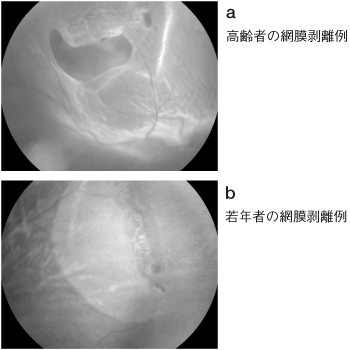

破れたりしわになったフィルムではまともな写真が撮れないように、網膜剥離が生じると視野や視力が障害されます。大半の網膜剥離は神経網膜に孔(裂孔)ができて起こるので、裂孔原性網膜剥離(図4-a.b)と呼ばれます。それに対して孔を伴わない網膜剥離もあり、非裂孔原性網膜剥離といいます。

図4